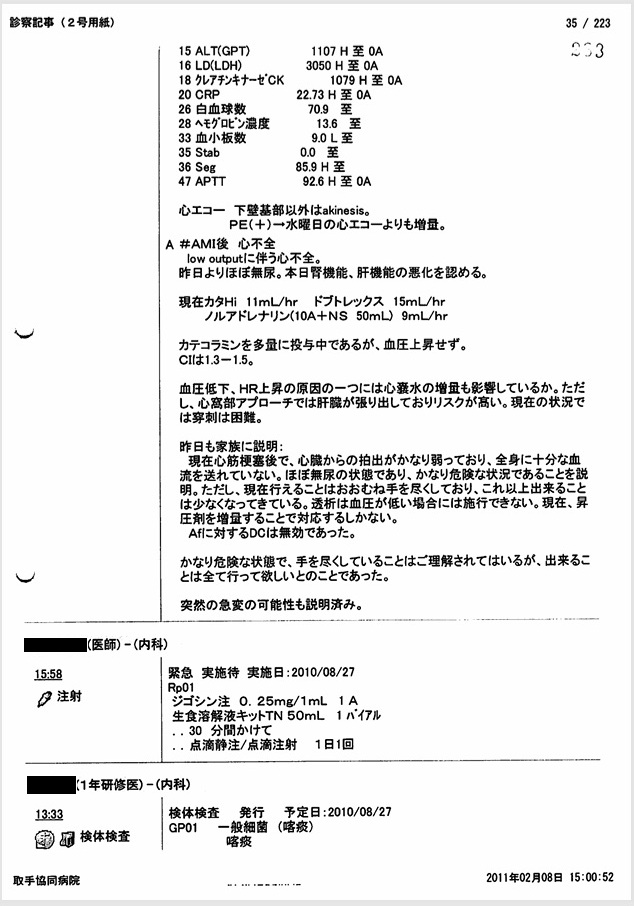

- 8月27日:改ざんを前提とした偽名患者の記録

人工呼吸器設定記録に「石川環」という偽名を用いて記載。改ざん記録の破棄を前提とした記録。

証拠:偽名が記載された人工呼吸器設定記録